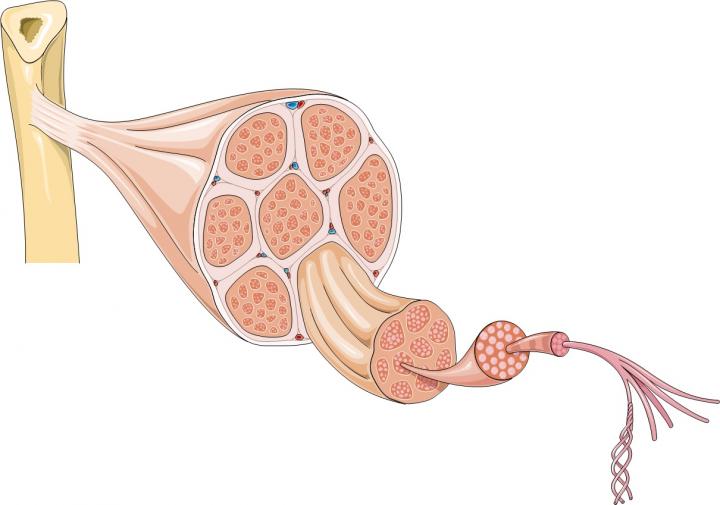

肌肉的大部分由肌纖維束形成,長細胞含有許多細胞核;但肌肉也含有許多其他類型的細胞,包括干細胞。干細胞是人體內置修復系統的一部分。它們可以產生祖細胞,也可以復制自己。骨骼肌含有一種稱為衛星細胞的干細胞。當肌肉纖維受損時,它們會向衛星細胞發送化學信號,告訴它們形成新的肌肉纖維或與現有纖維融合以修復損傷。同時,一些衛星細胞會自我復制,以確保有足夠的干細胞可用于在未來繼續修復和更換肌肉纖維。

干細胞治療肌營養不良癥的可能途徑:?中成血管細胞 (MAB) 樣細胞可由 iPS 細胞制成。在最近的一項研究中,將 MAB 樣細胞移植到小鼠體內,取得了一些積極的結果。需要更多的研究來確定該策略是否可以為患者帶來治療。

Emma Kemp 使用Servier Medical Art制作的肌肉結構主圖和說明 iPS 細胞在肌營養不良癥細胞療法研究中的應用?。Edwin P. Ewing, Jr 博士拍攝的杜氏肌營養不良癥患者的肌肉圖像,由美國衛生與公眾服務部公共衛生圖像庫提供?。Mike Kayser的肌纖維照片?,Wellcome Images。?

從中成血管細胞中生長的肌纖維由 OptiStem 和 Giulio Cossu 提供。